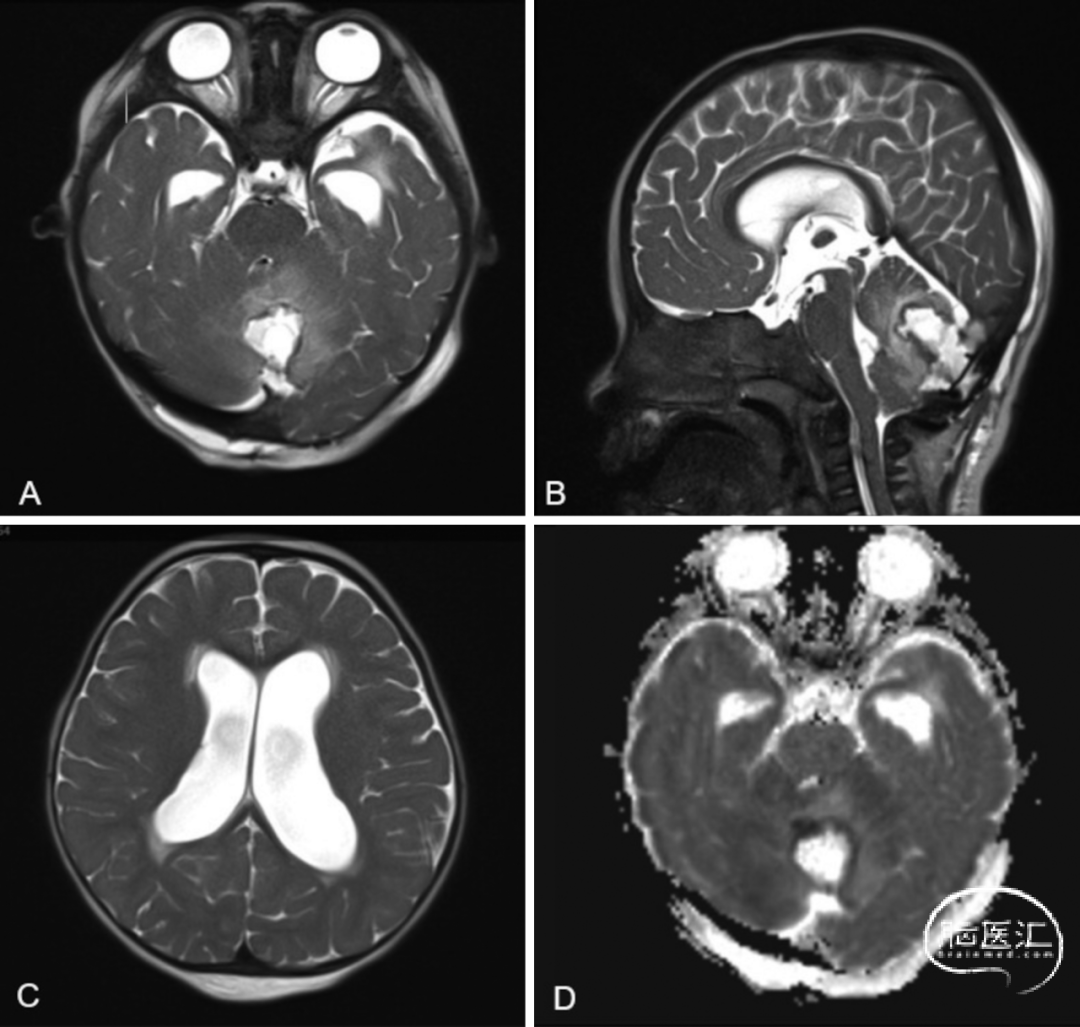

■ 脑部MRI显示后颅窝占位性病变(2.6×3×2.7cm),压迫小脑蚓部,伴幕上脑室扩大(图2)。因病变体积大、有占位效应,伴梗阻性脑积水及神经功能恶化,决定再次手术。

图2. 随访MRI检查显示小脑中线病变,伴继发性幕上脑室扩大,病变后部致密部分存在弥散受限,符合皮样囊肿表现。